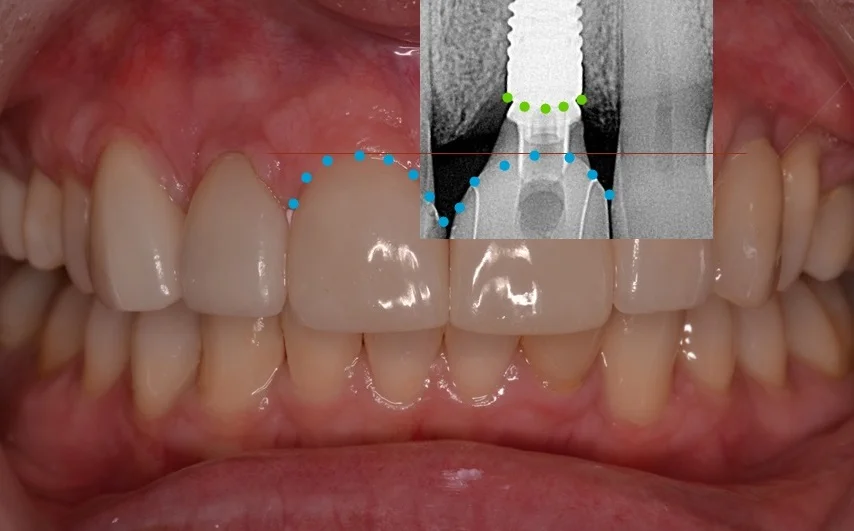

Implants in the Aesthetic Zone

With advances in implantology and our understanding of biology, biomechanics and restorative solutions, expectations from out patients and ourselves are at the highest they have ever been. This lecture will discuss implant placement, hard and soft tissue requirements,...

Dr. Robert Stanley’s Five Thread Guideline: The Science of Predicting Primary Stability

Primary stability remains the single most important predictor of implant success — yet for decades, clinicians have had no reliable way to forecast it before surgery. Most treatment plans still rely on bone density estimates, insertion torque, or tactile feedback...